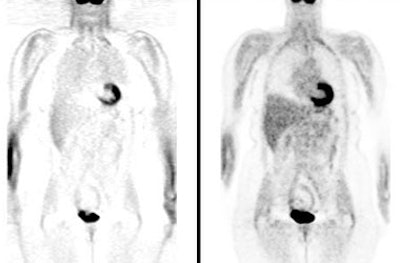

BGO versus LSO detector: The images below were acquired in 2D mode with a scan time of 5 min/bed emission and 3 min/bed transmission. The upper row of images were acquired on a BGO camera system and the lower row of images were acquired on a ECAT Accel LSO PET camera system. The data was reconstructed using normalized attenuation weighted OS-EM reconstruction. Image courtesy of Northern California PET Imaging Center, Sactamento, CA and CTI, The Power Behind PET. |